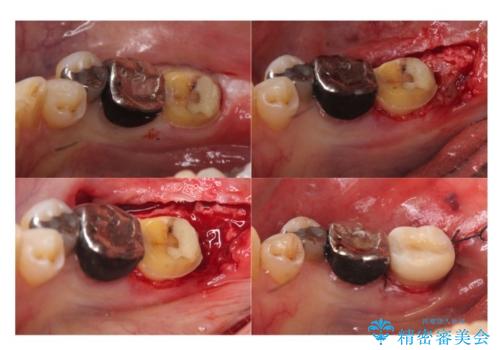

⑶5−6か月待つ

⑷最終形成、歯型とり

⑸クラウン装着

今回は、歯周外科手術を行い、歯ぐきの厚みを薄くし、また、歯槽骨の高さも整えて、歯周環境を整えました。

そうすることで、正確に歯型もとれ、精密なクラウンが製作でき、再度虫歯になる可能性を低くできます。